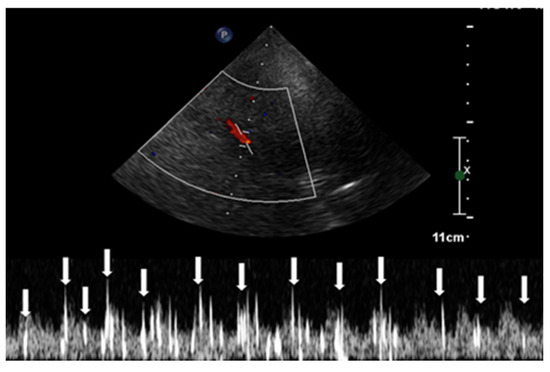

2.2.2. Contrast-Enhanced TCCD

2.2.3. Contrast-Enhanced Transesophageal Echocardiography